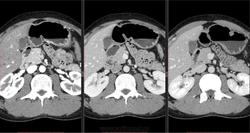

Случай коллеги. Пациент 33-х лет. Боли в эпигастрии, после злоупотребления алкоголем. С поджелудочной без проблем, интересно другое. 3 фазы с интервалом 30 сек между ними. Надеюсь, классическим рентгенологам будет интересно.

Обратите внимание на привратник. В первую фазу (сосуды выглядят белыми) картина отличается от двух других фаз. Вычтите перистальтику, что остаётся?

Скользящий пролапс слизистой желудка в луковицу.